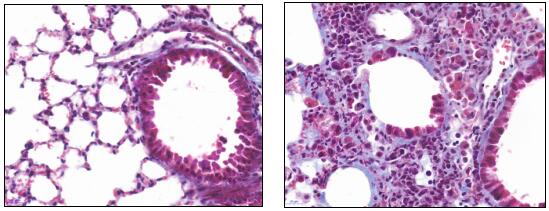

- 模型验证:通过肺组织病理学检查(如HE染色)、羟脯氨酸含量测定、肺脏系数测定等方法验证模型的可靠性。例如,肺组织中蓝色染色区域显著增加,表明肺纤维化模型构建成功。

- 肺纤维化模型发展时间:给药后第 7 天肺组织大多呈重度肺泡炎改变,肺泡腔及肺间质内有大量中性粒细胞浸润,部分肺泡腔破坏或消失,肺间隔内成纤维细胞和毛细血管增生,与正常肺组织对比差别明显;给药后第14天,肺纤维化开始形成。巨噬细胞、中性粒细胞等炎性细胞明显减少,成纤维细胞增多,肺泡间隔明显增厚,有胶原沉积。给药后第28天,多数小鼠发生弥漫性肺间质纤维化,肺间质被胶原纤维和成纤维细胞替代,肺泡壁破坏,肺大泡形成,但仍可见炎性细胞浸润。

特发性肺纤维化模型小鼠(右)相对于对照组小鼠肺部组织MASSON染色对比